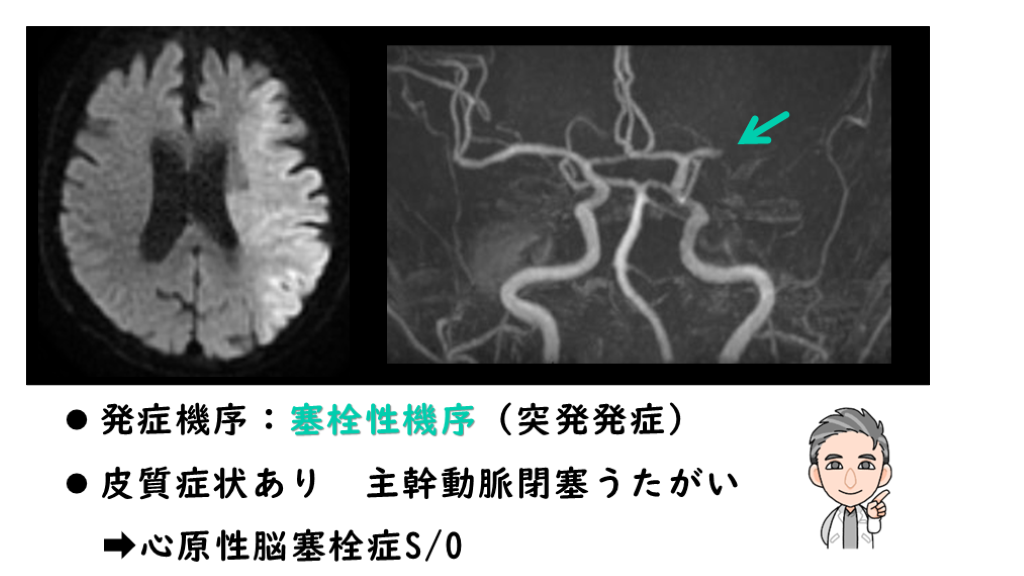

発症機序:塞栓性機序(突発発症) 皮質症状あり 主幹動脈閉塞うたがい  ➡心原性脳塞栓症S/O